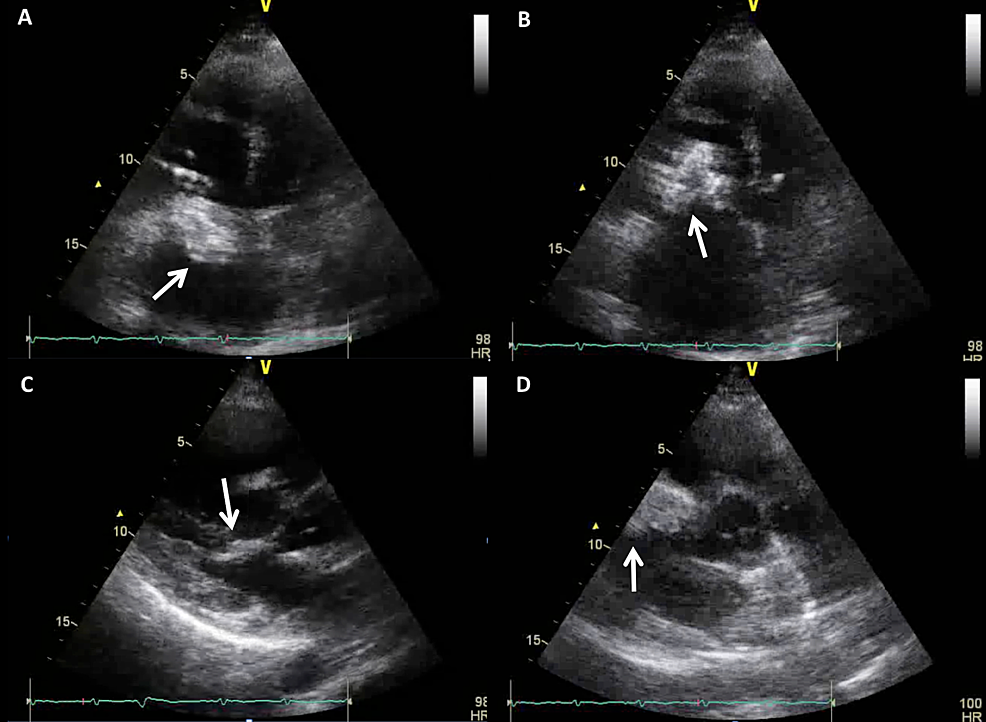

preoperative transthoracic echocardiography showing covered

findings-on-transthoracic-echocardiography.